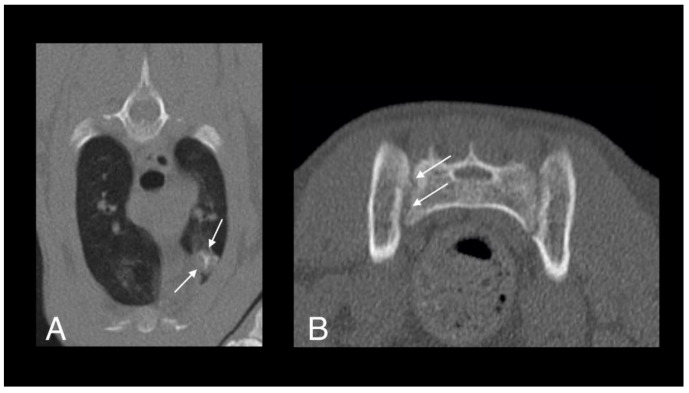

A full-body CT scan was performed. A large, poorly marginated, partially mineralized, and heterogeneously contrast-enhancing mass was identified along the pectoral region between the thoracic inlet and the sixth sternebra. Severe secondary osteolysis of sternebrae four and five was evident. The mass infiltrated the superficial and pectoral muscles bilaterally and extended dorsally within the thoracic cavity causing marked dorsal displacement of the heart and mild dorsal displacement of both cranial lung lobes (Figure 8A–C). A subtle lytic lesion was identified along the dorsal margin of the right scapula, with mildly contrast enhancing adjacent soft tissues (Figure 8D–F). Numerous well-marginated nodular soft tissue attenuating lesions, with associated heterogeneous contrast enhancement, were visible within the subcutaneous tissues of the ventral and dorsal thoracic wall. A generalized bronchial pattern was evident, with ill-defined areas of increased pulmonary attenuation, which was more pronounced in the cranial lung lobes. There was also regional lymphadenopathy.

Figure 8.

Computed tomography images in transverse plane of cat 2 with different reconstructions: bone (A,D), soft tissue (B,E), and soft tissue after contrast medium administration (C,F). Images A–C are at the level of the 4th and 5th sternebrae. There is a large, poorly marginated, partially mineralized and heterogeneously contrast enhancing mass infiltrating the adjacent pectoral musculature (white long arrows). Note severe secondary osteolysis of the sternebrae (black long arrows). Marked dorsal displacement of the heart is also visible (asterisk). Images D–F are at the level of the scapulae. Along the dorsal margin of the right scapula a subtle lytic lesion and mild contrast enhancement in the adjacent soft tissues are visible (short white arrows). The dorsal margin of the left scapula is normal (short black arrow).

Monitoring has continued. Four weeks later, the patient’s skin lesions had continued to improve. Repeated hematology and serum biochemistry were performed and there were no changes suggestive of hepatotoxicity secondary to rifampicin therapy, or neutropenia or thrombocytopenia secondary to pradofloxacin therapy. Fourteen weeks after starting triple antibiotic therapy, the skin lesions were almost completely healed and on a repeated full-body CT scan there was mild regression of the aggressive soft tissue mass infiltrating the pectoral muscles and resolution of the lytic lesion in the right scapula. However, there was only very mild improvement in the broncho-interstitial lung pattern. Daily treatment with rifampicin and azithromycin was continued but, on alternate days, the doses were doubled to 17.5 mg/kg PO and 15 mg/kg PO, respectively. Pradofloxacin was continued at the same dose and interval as before. A total of ten weeks later (24 weeks after starting treatment), the patient was tolerating the increased dose of rifampicin and azithromycin, and full-body CT showed further regression of the sternebral mass and moderate regression of the bronchial lung pattern. N-acetyl cysteine (NAC) (600 mg/cat PO q12 h; Essential Healthcare) was added to the treatment protocol to try to speed resolution due to its direct antimycobacterial effects as well as hepatoprotective activity [52,53]. The patient presented 21 weeks later (45 weeks after starting treatment) for repeated examinations. Hematology and serum biochemistry findings were unremarkable and full-body CT scan showed further improvement of the size and appearance of the sternebral mass and almost complete resolution of the pulmonary changes (Figure 9). There was moderate remodeling of the sternebrae, with much more solid bone present and no new osteolytic or proliferative changes. The soft tissue component of the lesion within the pectoral muscles was also markedly reduced in size and exhibited less contrast uptake. Antimicrobial therapy was ceased at this point, in part due to the cat becoming progressively reluctant to take oral medication. Careful monitoring of the patient has continued and there has been no evidence of relapse of active disease; a repeat CT scan three and a half months after stopping treatment showed minimal further change in the appearance of the lesions.

Figure 9.

Computed tomography images in transverse plane of cat 2 with different reconstructions: bone (A), soft tissue (B), and soft tissue after the administration of contrast medium (C). Images are at the level of the 4th and 5th sternebrae. Note moderate remodeling of the sternebrae with much more solid bone and no new osteolytic or proliferative changes (black arrows). The soft tissue component of the lesion within the pectoral muscles is markedly reduced in size and exhibits less contrast uptake (white arrows). Compare to Figure 8, images were taken at the same level.